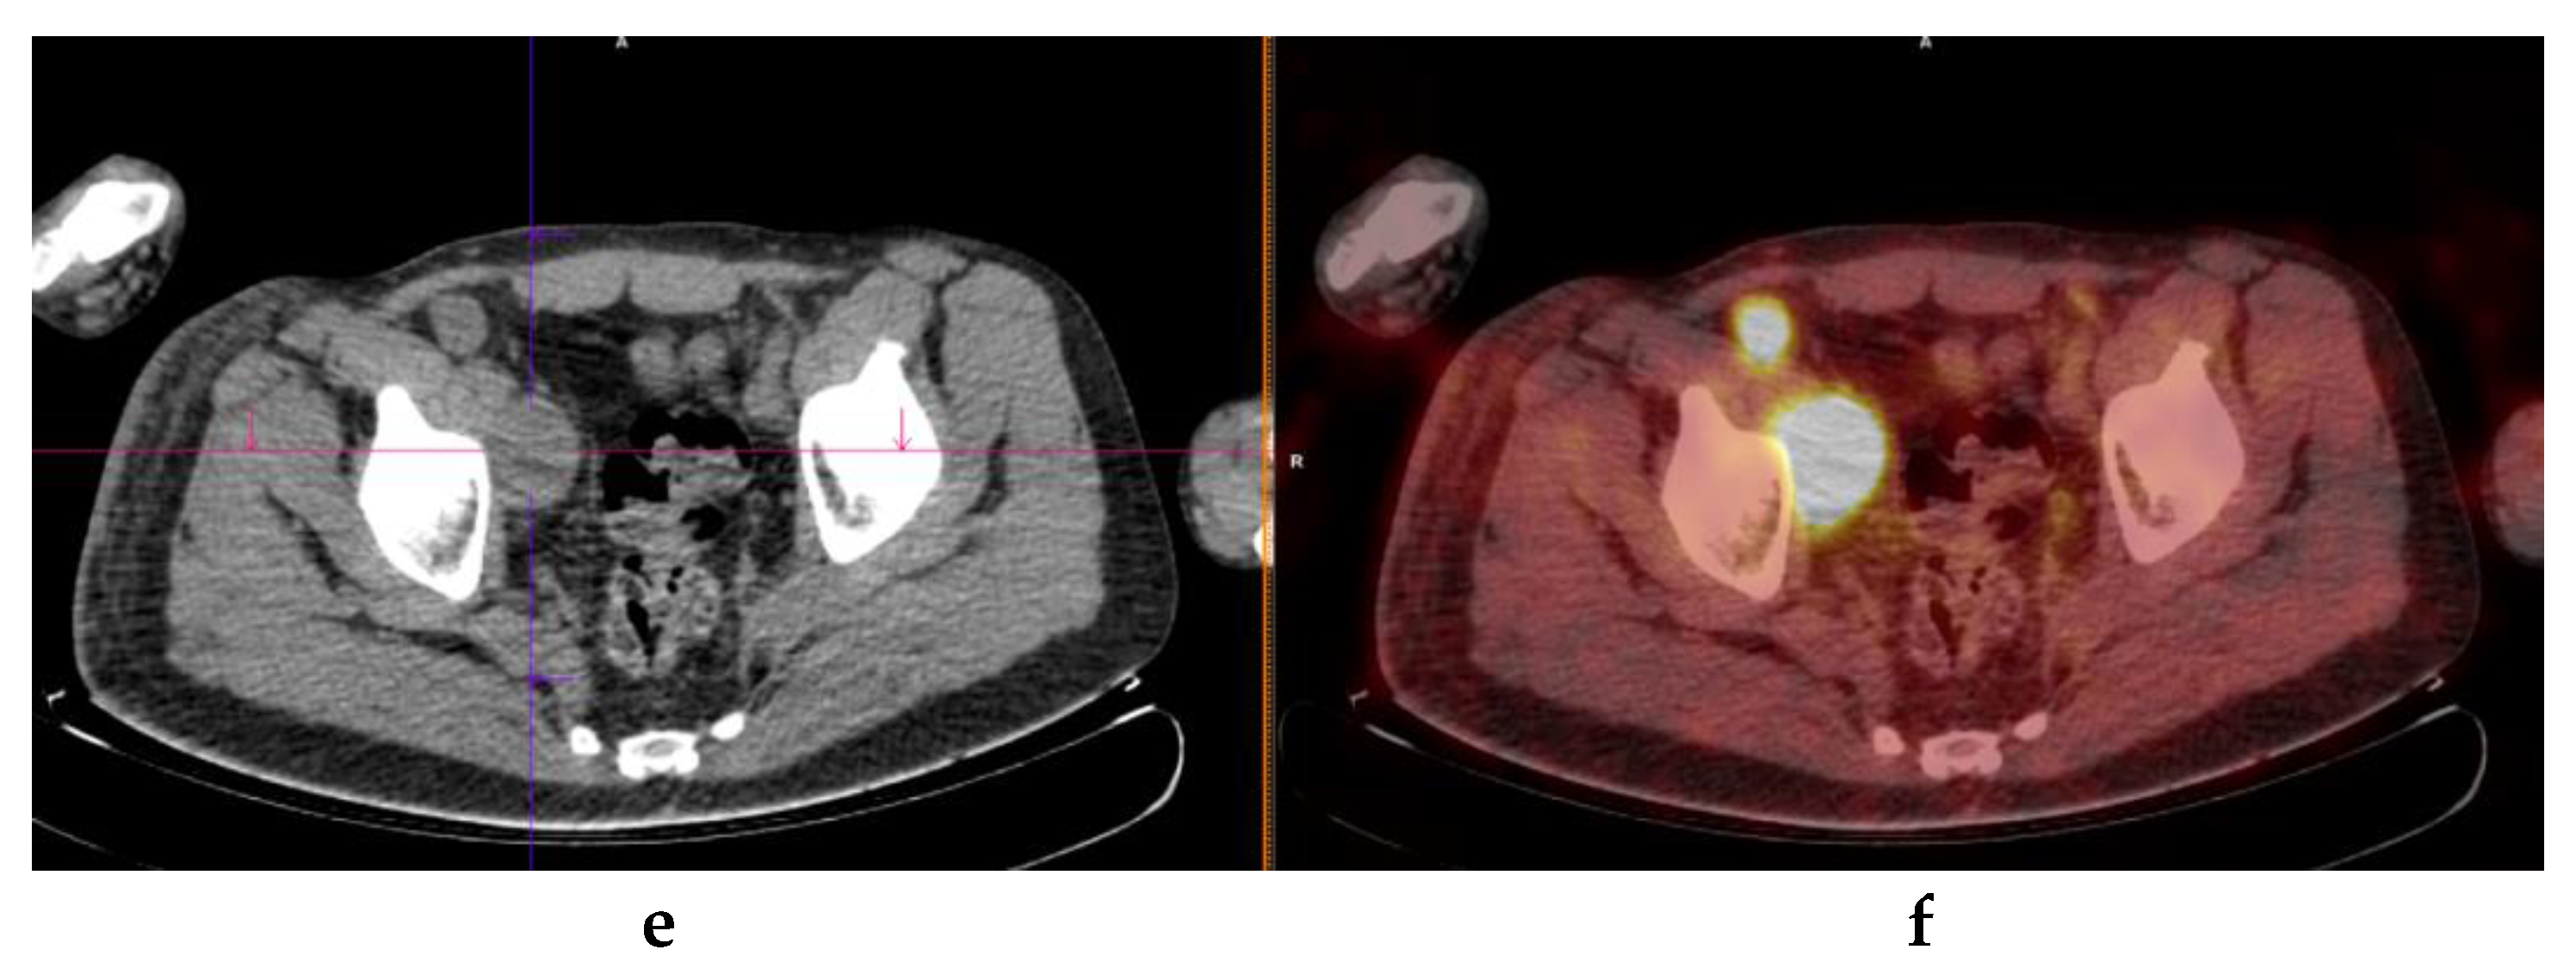

3.6. Per Site Analysis of FDG PET/CT DA for Extra-Cutaneous Lesions

| Digestive tract | 2 | 3 | 60 | 10 | 17% | 95% | 40% | 86% | 83% |